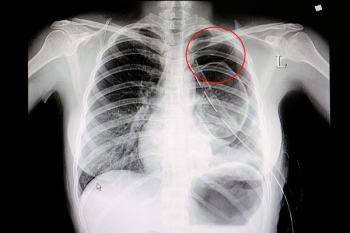

BraveCX, an artificial intelligence (AI)-enabled software, reportedly has an area under the curve (AUC) of 98 percent for detecting pneumothorax on chest X-rays.